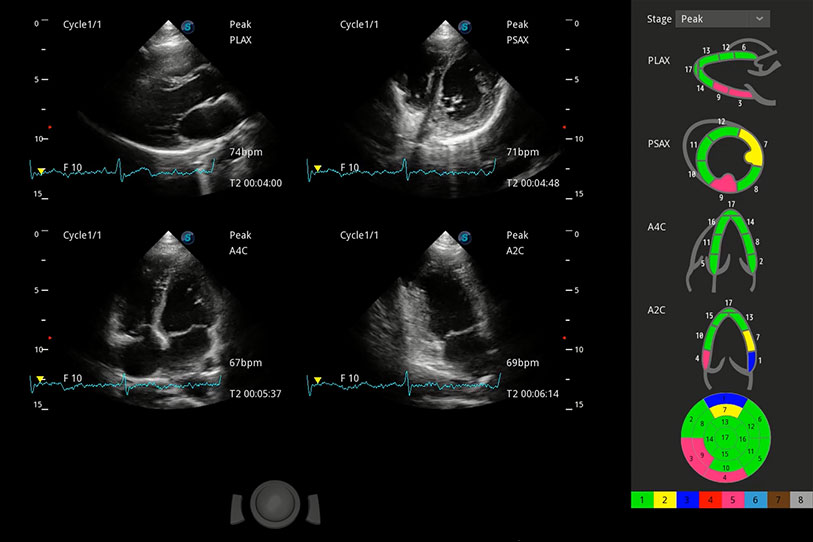

能夠基于左心室壁追蹤和辛普森法,自動計算射血分?jǐn)?shù),支持多個可移動點(diǎn)描跡,與手動測量相比,極大節(jié)省了動物醫(yī)生的時間和精力。

具備多種協(xié)議可選,同時支持17階段劃分法和專業(yè)的SE報告。